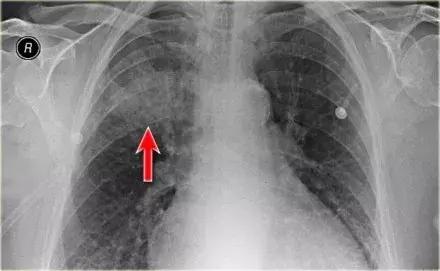

2.病例二

➢ 胸部X线显示,肺右上叶出现密度增加的模糊阴影,肺体积没有缩小

➢ 右肺门在正常的位置

➢ 箭头所示为空气-支气管征

➢ 结合适当的临床诊断,很像大叶或肺段性肺炎

➢ 然而,如果患者出现体重减轻,或症状时间持续较长,可能存在慢性实变的病因。

➢ 诊断结果为,肺炎链球菌引起的急性大叶性肺炎

图4 肺炎链球菌引起的急性大叶性肺炎